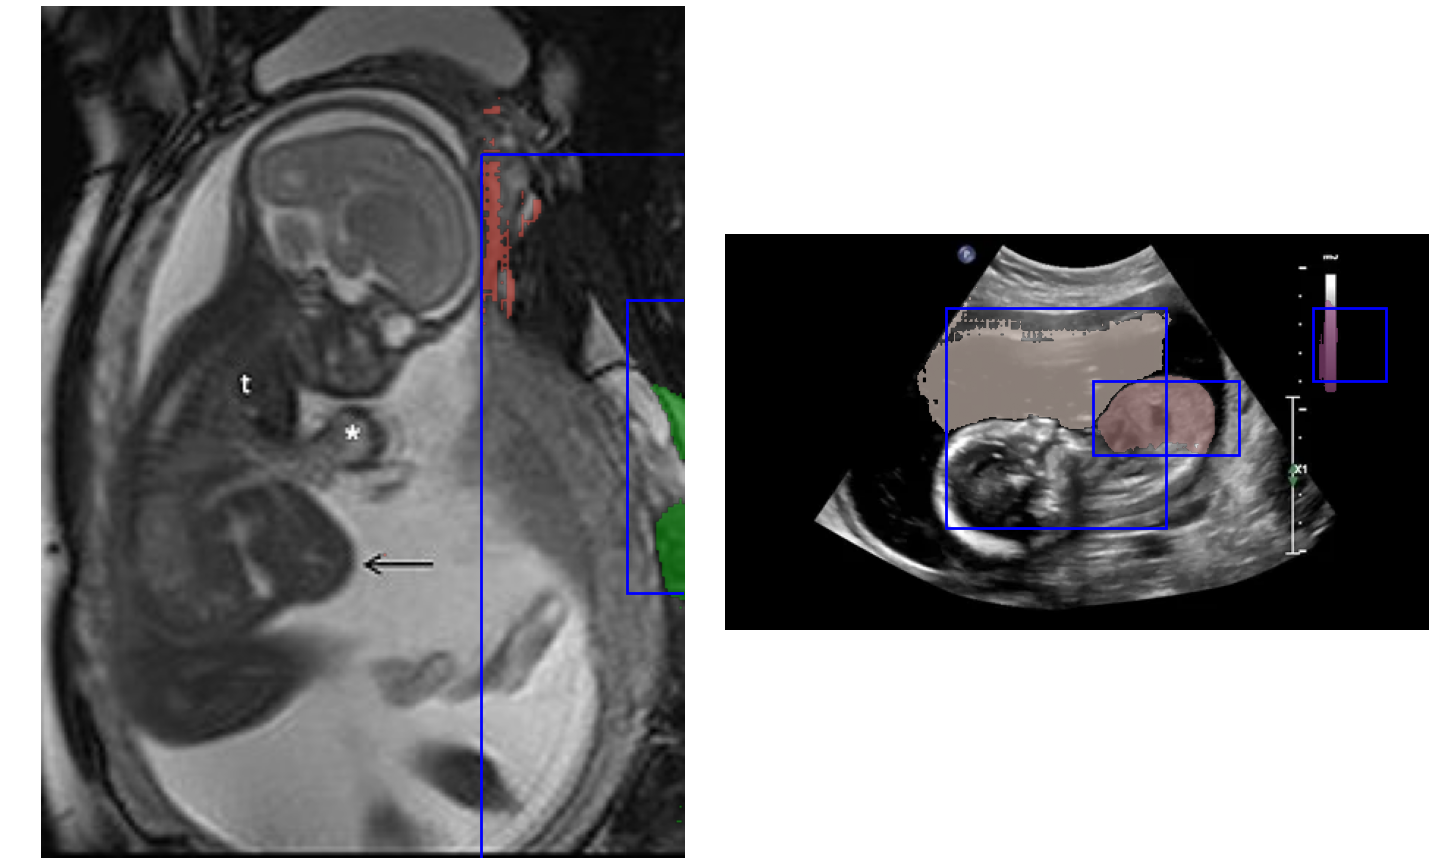

Ultralytics

Roboflow

OpenCV

My Portfolio

Some of the projects I've worked on.